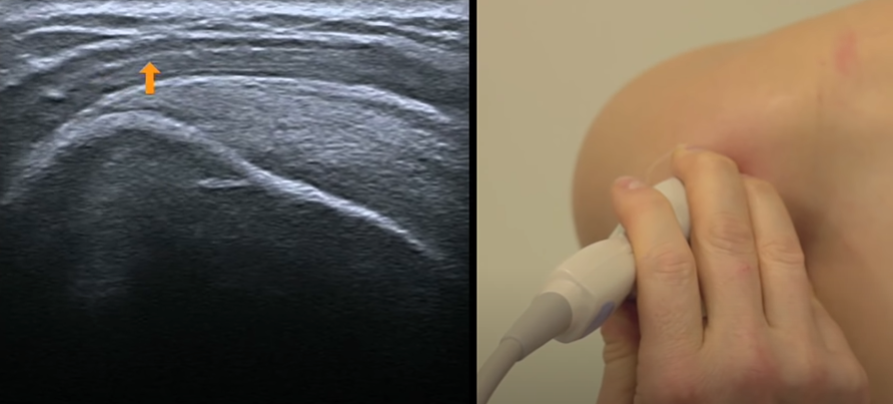

Face antérieure

Long biceps

- Epaule en position neutre à 90° en supination

- Coupe axiale et longitudinale

- Incliner la sonde pour le suivre en axial dans sa partie supérieure quand il vire

- Tendon = Hyperéchoène et sujet à l’anisotropie (Change avec l’inclinaison de la sonde)

Entre la grande tubérosité (GT) et la petite (LT)

Coupe axiale obliquée supérieurement

Coupe longitudinale